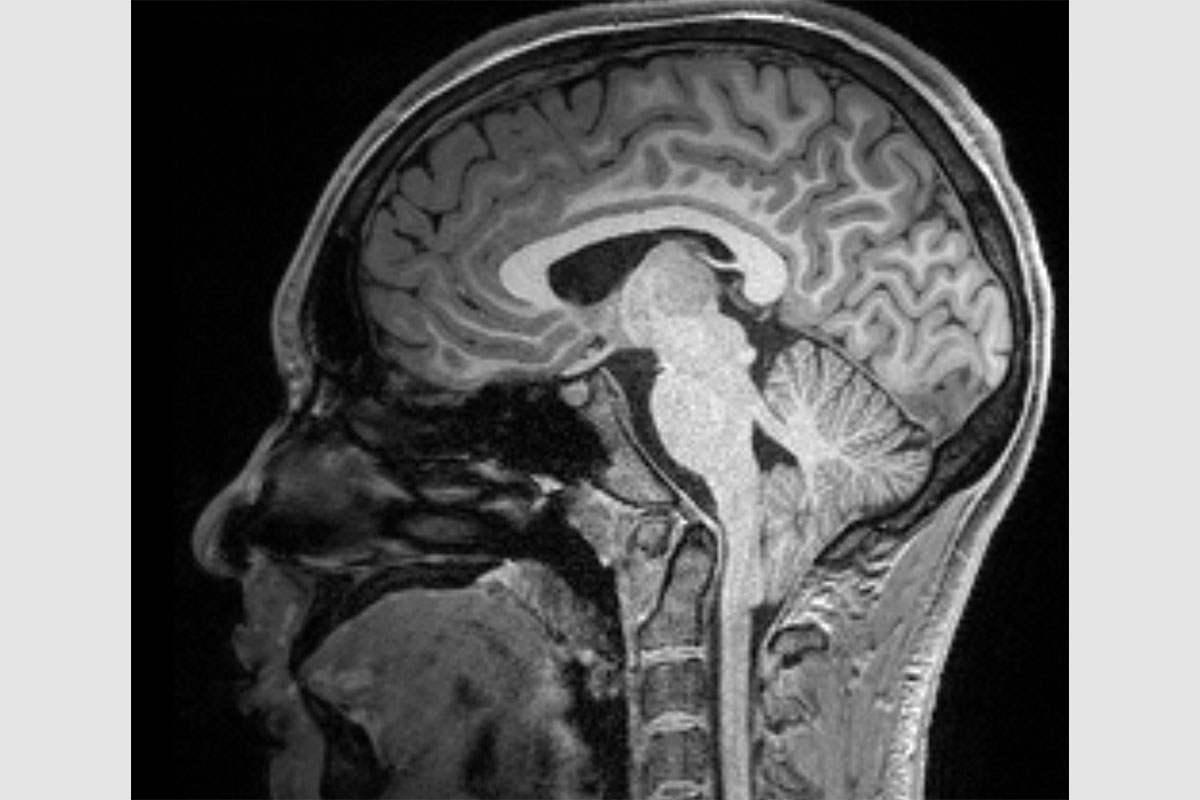

Chiari type-1 malformation affects roughly 4% of the population and is characterized by the cerebellum protruding through a gap in the skull. The condition's unpredictable symptoms have made standardized treatment elusive. Researchers at Washington University in St. Louis have used artificial intelligence to identify three sub-types of Chiari type-1, providing a basis for more tailored treatment approaches. **Cluster 1** patients, often female, tend to experience chronic headaches; **Cluster 2** patients, diagnosed early, face issues like muscle control; while **Cluster 3** frequently involves spinal deformities requiring surgery. Utilizing data from the extensive Park-Reeves Syringomyelia Research Consortium, AI tools sifted through complex datasets to define these clusters, paving the way for evidence-based treatment guidelines. This collaboration across neurosurgery and computer science promises to transform the field by leveraging vast electronic health records for innovative patient care solutions.